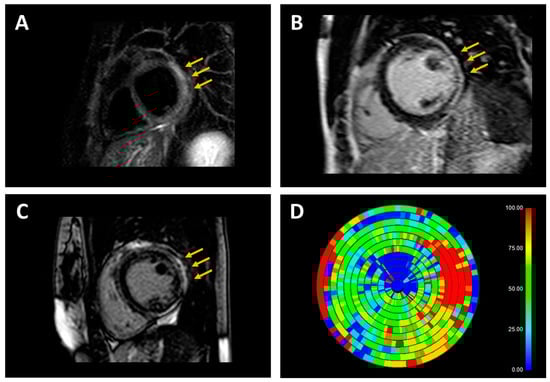

- Peretto, G.; De Luca, G.; Villatore, A.; Di Resta, C.; Sala, S.; Palmisano, A.; Vignale, D.; Campochiaro, C.; Lazzeroni, D.; De Gaspari, M.; et al. Multimodal detection and targeting of biopsy-proven myocardial inflammation in genetic cardiomyopathies: A pilot report. JACC Basic Transl. Sci. 2023; ahead of print. [Google Scholar]